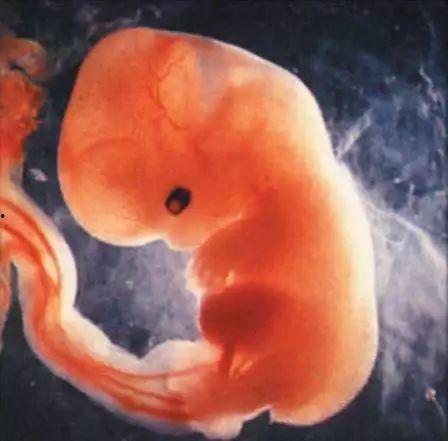

一、怀孕三个半月胎儿图片:初见宝宝的小模样

当你怀孕三个半月时,宝宝的成长已经进入了一个新的阶段。这个时候,通过超声波检查,你就可以看到宝宝的小模样了。让我们一起来看看这些珍贵的图片吧!

1. 头部特征:三个半月的胎儿,头部已经占据了身体的大部分。宝宝的眼睛开始形成,虽然还是闭着的,但已经有了眼睑的轮廓。耳朵的位置也逐渐清晰,小鼻子也开始显现。

2. 身体比例:这个时候的宝宝,身体比例开始变得协调。四肢开始伸展开来,手和脚的指(趾)甲也开始出现。宝宝的脊柱和肋骨也渐渐成形。

3. 面部表情:虽然宝宝的脸部表情还不是很明显,但通过图片,我们可以看到宝宝的嘴巴和鼻子已经有了大致的形状。